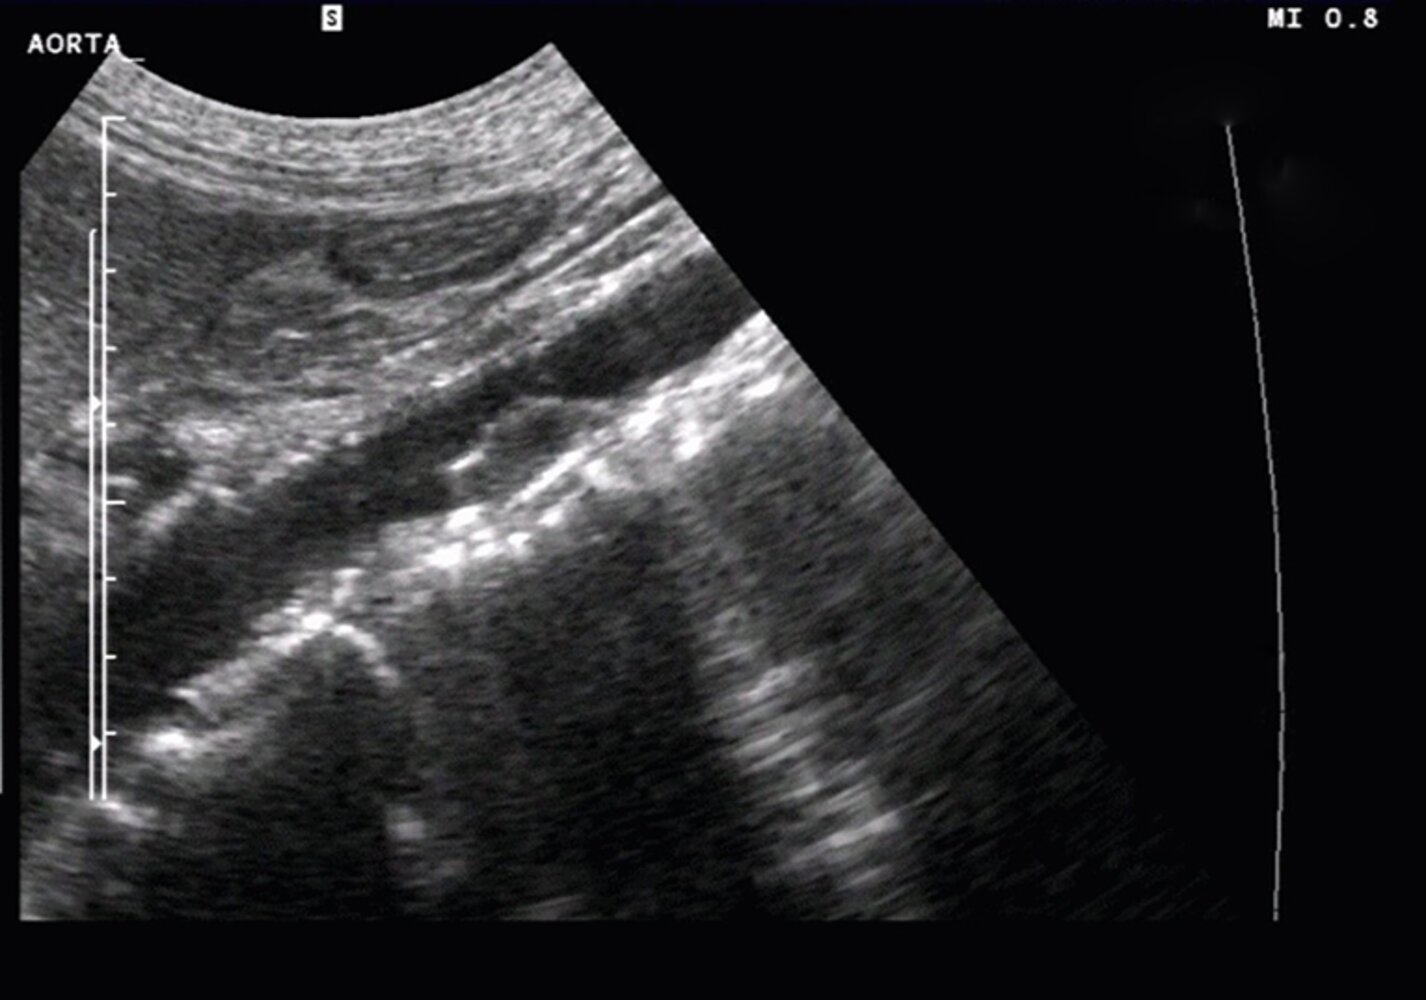

- Abdominal aortic aneurysm, thoracic aortic aneurysm

- Weakening of vessel wall: arterial aneurysm or dissection (e.g., aortic aneurysm, aortic dissection)